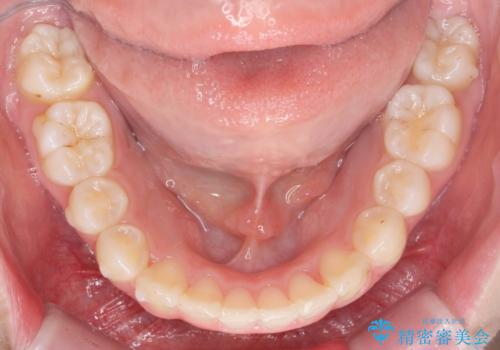

口腔内の清掃状態の良さに加えて、マウスピースを毎日きっちりと装着し、しっかりと使用していただけたことからワイヤー矯正は行わずにきれいに歯並びを治すことができました。

途中顎位が変わり、マイクロインプラントを併用した上顎臼歯の遠心移動が必要となったため治療が長期化しました。